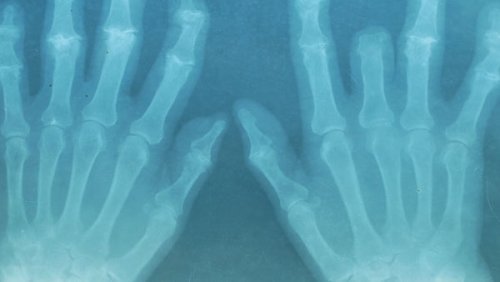

As doenças musculoesqueléticas são cada dia mais comuns. Por isso, recomendamos o uso dos óleos essenciais para evitar as dores dos músculos e articulações.

Os detonadores são muito variados: desde lesões após fazer exercício ou uma higiene postural deficiente até a deterioração própria da passagem do tempo.